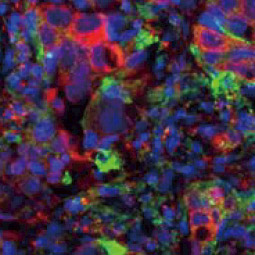

| 动物病毒的感染是通过病毒与宿主细胞结合而引发的,由于不同病毒之间存在相当大的复杂性和可变性,因此描述后续的病毒感染机制是一个深入研究的领域。然而,此过程(尤其是某些包膜病毒)的一般流程涉及以下步骤: (1) 病毒附着于宿主细胞受体,(2) 细胞信号通路激活,(3) 胞吞作用,(4) 细胞膜渗透和细胞内运输,(5) 病毒基因组脱壳。然后,病毒基因组能够在感染细胞内表达、复制、包装和释出再感染其他细胞,了解感染过程中病毒/宿主细胞相互作用的分子事件,对于找到潜在的药理干预靶标至关重要。 GeneTex为传染性疾病研究提供优质的抗体,包括病毒附着、内化和渗透等,这些抗体经过各种应用验证,以帮助您在这个令人兴奋的领域中努力,请查看下面显示的热门研究产品,并访问GeneTex网站以获取更多信息和完整的产品列表。 |